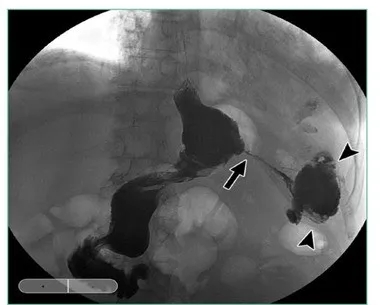

瘘发生的最常见部位

在袖管胃上三分之一地方,

由于袖管胃缩窄或狭窄,

导致胃内爆破压升高,

在靠近食管胃结合部附近的

袖管胃缝钉线上,因这里相对比较薄弱,

容易发生破裂而形成瘘。

图上显示胃底切割线交叉处是瘘发生部位,

梗阻通常发生胃切迹呈角的地方。

Leaks from Sleeve Gastrectomy

A leak from the SG portion of the procedure has historically been the most common area for a leak after a duodenal switch. The incidence has been reported as 1 to 4 percent, depending on the study evaluated. Over the last 5 to 10 years, the incidence has dropped as surgeon experience has increased in performing the SG as a stand-alone procedure. The most common area for a leak is in the upper one-third of the sleeve due to narrowing or stricture of the sleeve at the incisura angularis (Figure 2). This will cause an increase in pressure in the sleeve with a blowout at the upper portion of the staple line near the gastroesophageal junction since this is the weakest point in the sleeve. The treatment of a sleeve leak in the acute setting without a significant obstruction involves a washout of the affected area with resuturing or restapling of the sleeve. Many of these can heal completely if addressed early enough with minimal contamination. In the chronic setting or with a chronic fistula, it gets a bit more complicated. Nutritional support and antibiotics are required initially, combined with adequate drainage. Drains can usually be placed via a surgical approach or with the aid of interventional radiology, but recent studies have shown that drainage can also be facilitated with endoscopic techniques, such as an endoscopic wound vac or endoscopic septotomy. The most important aspect though for definitive treatment is to look for and relieve the obstructive point, which is usually at the angularis. This can be done with placement of an endoscopic stent, but in reticent cases, eventual surgical resection and Roux-en-Y reconstruction might be required.